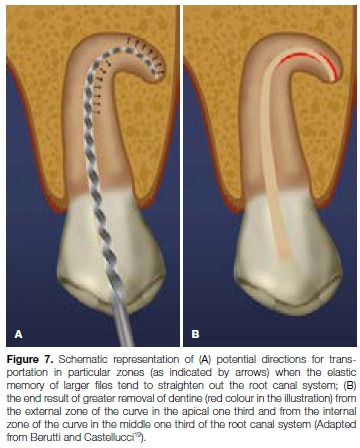

Canal transportation is a sustained deviation from the original axis of the canal during root canal instrumentation (Figures 7a and 7b).

Apical canal transportation is described as the removal of canal wall structure on the outside curve in the apical half of the canal due to the tendency of files to recover to their original linear shape during canal preparation.15

As a result, the main axis of the root canal is transported away from its original axis. Other terms for canal transportation include "canal straightening" and "zipping".4

Stiff endodontic instruments, particularly large-sized stainless steel files, tend to exert elevated lateral forces in curved canals and can result in straightening, especially in the middle and apical thirds.16